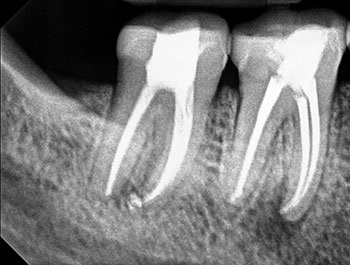

Fig. 3: Recall PA.

The patient returned in three months, when resolution of symptoms, healing of the deep probing defect and bone regeneration were confirmed. The tooth was obturated, and a foundational restoration was placed before the rubber dam was removed. Fourteen years of follow-up confirmed long-term periradicular health. The amount of appreciation and gratitude that this patient expressed reminds us that each individual tooth demands our best efforts.